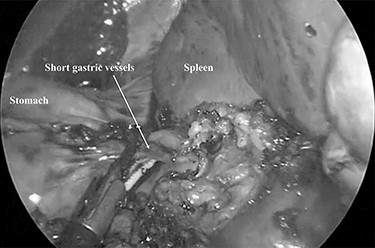

The patient was placed in the right lateral decubitus position. The standing positions of the surgeon and the assistant were on the right or left of the patient depending on the surgical site. Initially, a 12-mm port was introduced through the lateral margin of the left rectus abdominis muscle at the level of the umbilicus. After establishment of pneumoperitoneum with an intra-abdominal pressure of 10 mmHg, two 3-mm ports were inserted in the left upper quadrant at the subxiphoid and left subcostal margin along the mid-axillary line. The accessory spleen was carefully explored through the abdomen. The spleen was mobilized from the lower to upper direction. The initial dissection involved release of the lower pole of the spleen with dissection of the splenocolic ligament, and the spleen was freed from the splenorenal ligament toward the posterior aspect of the splenic hilus using laparoscopic coagulating shears under the guidance of a 3.3-mm needlescope (Karl Storz SE & Co. KG) (Fig. 2). Subsequently, short gastric vessels (Fig. 3) were divided, and the upper pole of the spleen was mobilized with the division of the splenophrenic ligament. Then, the splenic hilus was divided using a linear stapler (Fig. 4). The isolated spleen was then placed in an impermeable bag (Endo-Catch II; Covidien Co. Ltd.) and extracted via a 12-mm port after morcellation using the placenta forceps without extending the initial 12-mm incision (Fig. 5). After irrigation with normal saline and confirmation of hemostasis around the resected area without inserting a suction drain, only the 12-mm port site was only closed, and the 3-mm port sites were left open.

The spleen was freed from the splenorenal ligament using laparoscopic coagulating shears.